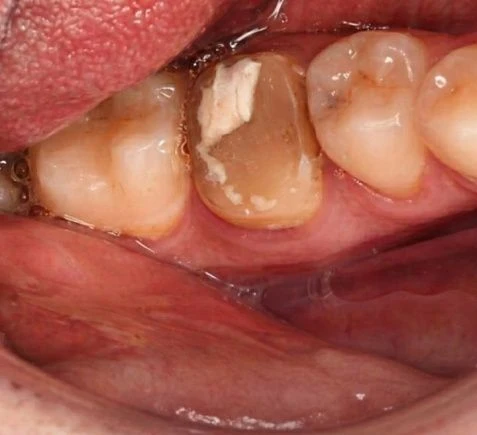

- Повреждение дентина кариесом или в результате механического воздействия

- Сильное разрушение коронки

- Трещины, сколы эмали

- Наличие здорового корня при полном разрушении коронки